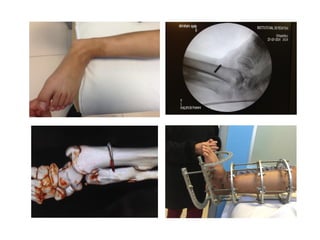

12.08.20

FOLLOW UP

25.09.21

17.11.20 25.11.20

25.01.21

18.03.2021

19.03.21

13.05.21

27.05.21